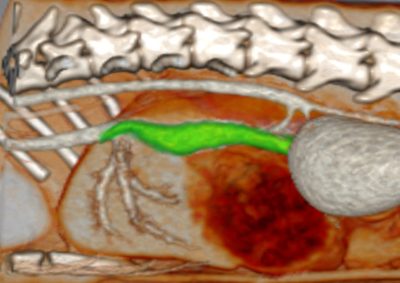

軟部組織外科 注意 ボタンをクリックした先に、治療中および手術中の画像が説明で使用されている場合がございます。 そのような画像に弱い方は閲覧なさらないようお願いいたします。 軟部組織外科 異物による唾液腺の穿孔 軟部組織外科 犬の尿管結石に対する結石摘除 救急・集中治療軟部組織外科 猫の尿管結石に対する尿管切除吻合術#11 軟部組織外科 PSS 犬の門脈体循環シャント 軟部組織外科 猫のPSS 軟部組織外科救急・集中治療 胆嚢摘出 軟部組織外科 予防的胃固定術 Lap−Gastropexy 軟部組織外科 特発性出血性心タンポナーゼ 軟部組織外科 猫の腎膿瘍 軟部組織外科 犬の特発性乳び胸 軟部組織外科 短頭種気道症候群 軟部組織外科 犬の腟脱 <«789101112131415> 症例カテゴリー 放射線治療整形外科軟部組織外科脳神経外科内科腫瘍外科救急・集中治療リハビリテーション科腫瘍内科内視鏡科脳神経科呼吸器外科中医・漢方猫の腎移植循環器科